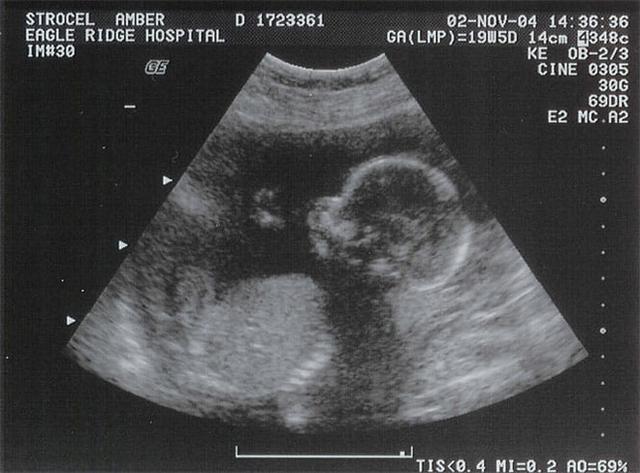

Ở tuần thai thứ 21, chị Briony đi siêu âm và nhận được thông tin mình đang mang bầu một bé gái. Thế nhưng, hạnh phúc ngắn chẳng tày gang, bởi chỉ vài tuần sau, hai anh chị đã phát hiện ra một tin vô cùng sốc.

Kết quả siêu âm cho thấy đứa trẻ đã ngừng phát triển ở tuần thứ 22.

Tại đây, các bác sĩ thông báo cho chị Briony và anh Mike rằng, đứa trẻ trong bụng đã bị ngừng phát triển từ tuần thai thứ 22. Tuy nhiên, em bé vẫn còn sống. Các bác sĩ nhận định đây là trường hợp cực kỳ hiếm gặp. Tin sốc đó đã khiến chị Briony và anh Mike vô cùng bàng hoàng.